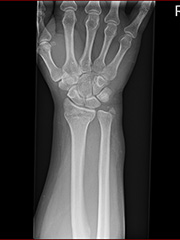

【注意】グロ画像

警告はしますが隠すことができません。すみません。

救急病院で撮ったレントゲン写真のCD-Rをもらったのであげ。

右下腕部のレントゲン写真

橈骨のところ、真横に線が入っているのが見えるかなー?